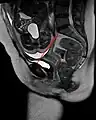

- Conjugata vera as measured on sagittal MRI